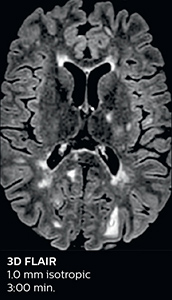

The abbreviated MS protocol for brain is only around 9 minutes, so in case of suspected multiple sclerosis, one or two more advanced sequences may be added, such as PSIR (phase sensitive inversion recovery) or susceptibility-weighted sequences to help us make more confident diagnoses in these inflammatory cases.

In this example, the optional 3D multishot susceptibility weighted sequence with 0.6 mm isotropic voxels is 2 lesions with a central vein sign (arrows) and one lesion with a phase-rim sign (arrowhead). The total scan time, including SmartBrain and axial PD/T2 3mm, is 11:10 min. and is 18:30 min. with the optional 3D PSIR and 3D SWI multishot included.

“In multiple sclerosis patients, we increasingly include a multishot susceptibility sequence [3] in our routine cases, thanks to the shorter scan times. Our abbreviated MS protocol for brain is around 8 to 9 minutes, so we can ask for one or two additional sequences to visualize the central veins, or to get an additional contrast to better depict posterior fossa lesions. In cases of white matter lesions of unknown significance on FLAIR images, for example when we see high signal hyperintensities in the brain, we can add on more advanced sequences such as PSIR (phase sensitive inversion recovery) or susceptibility-weighted sequences to help us in distinguishing between MS and nonspecific or vascular abnormalities in these inflammatory cases.”